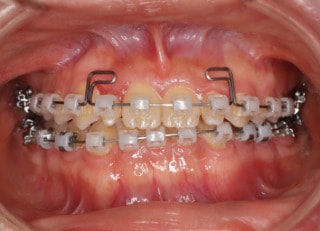

治療後(2年11ヶ月後)

治療開始から25ヶ月後